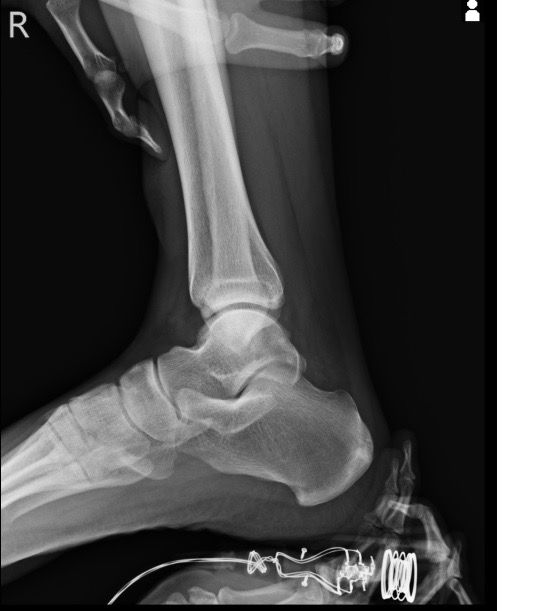

복숭아뼈 골절이 맞는 걸까요 엑스레이 사진 올립니다

3월1일 다리 접질린 후 약간의 통증과 심한 붓기 멍으로 3월7일 병원 방문. 정형와과에서 엑스레이 초음파 검사 후 골절진단 받았네요 그뒤 반깁스란 목발 받고 3일 후 다시 반깁스 하고 왔습니다 사진상에는 뼈가 떨어진 부분이 없는데 미세골절이라 그럴까요

• 1번 째 사진

사진상으로는 정확한 상태를 확인하기 어려우나 병원에서 골절 진단을 받으셨다면 골절일 가능성이 높고 엑스레이에서 뼈가 떨어진 부분이 보이지 않는다면 미세골절일 가능성이 높습니다.

미세골절 같은 경우 엑스레이상으로는 뚜렷하게 보이지 않기 때문에 검사 결과로 진단 할 수 있습니다.

엑스레이에서 뼈가 떨어진 부분이 보이지 않는다면 미세골절일 수 있습니다. 미세골절은 엑스레이에서 뚜렷하게 보이지 않지만 증상과 검사 결과로 진단할 수 있습니다.

네, 골절에는 반드시 뼈가 떨어지는 변화가 일어나는 것은 아닌데요, 미세골절의 경우에는 큰 변화가 발생하지는 않습니다.